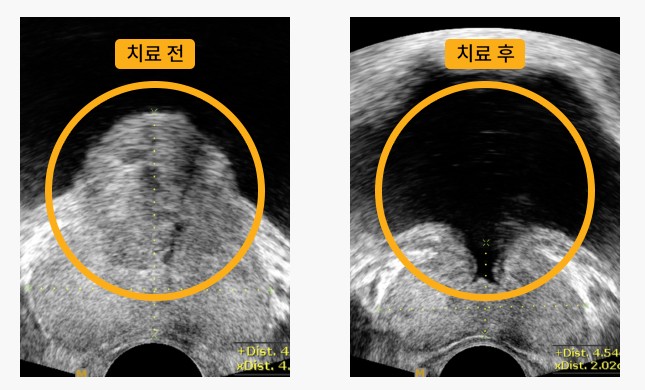

■ 전립선 축소 치료

중등도 이상의 증상이 있는 경우, 전립선을 축소시키는 치료 방법이 고려될 수 있습니다.

전립선 축소를 위해 알파-차단제와 5-알파-환원효소 억제제가 함께 사용될 수 있으며, 수술적인 절차인 전립선 전체적인 축소나 전립선 절제술도 선택될 수 있습니다.